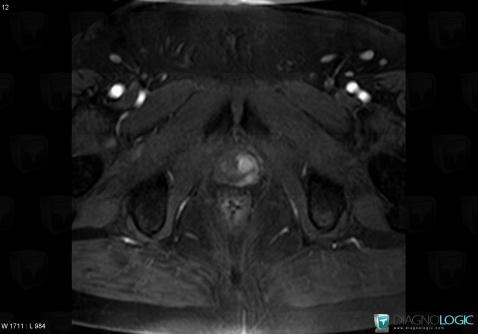

Prostate cancer, Prostate, MRI

Here is the specific information in the key image above:

- Diagnosis Prostate cancer, Location(s) Prostate, with gamuts